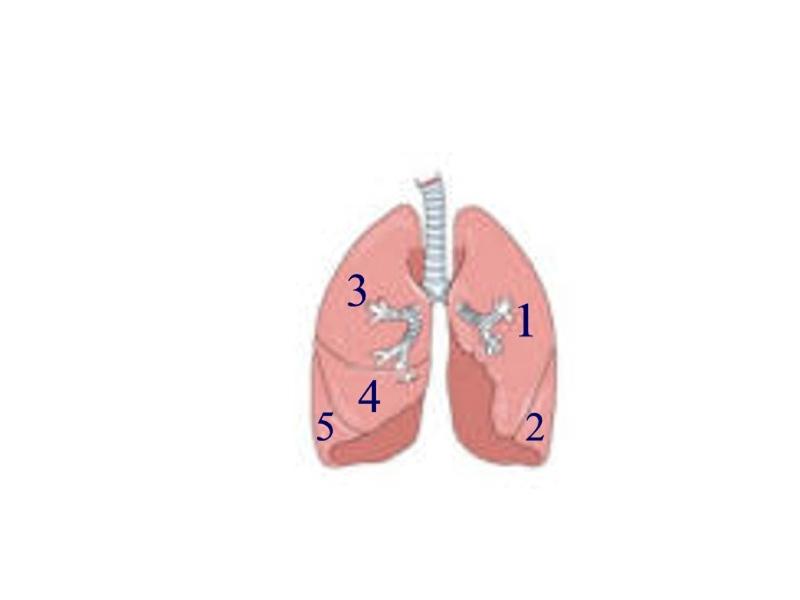

Bronchioles

Horizontal fissure (of right lung)

Left/right oblique fissue (of lung)

Left/right primary bronchus/bronchi

Secondary bronchi

Upper/middle/lower lobe (of lung)